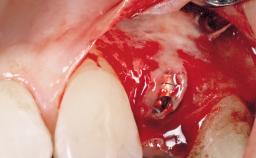

Bone Augmentation | Horizontal|Simultaneous |

Augmentation Materials | Autogenous chips|Xenogenous|Membrane |

Bone Volume | Deficient horizontally, allowing simultaneous augumentation |